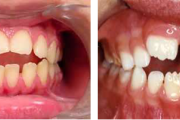

Ravijärgne seis. Jäävhammas on täielikult lõikunud.

) Röntgenülesvõte. Ülemise esimese jäävmolaari lõikumine on takistatud 2. piimamolaari tõttu

Esimese jäävmolaari ektoopiline lõikumine